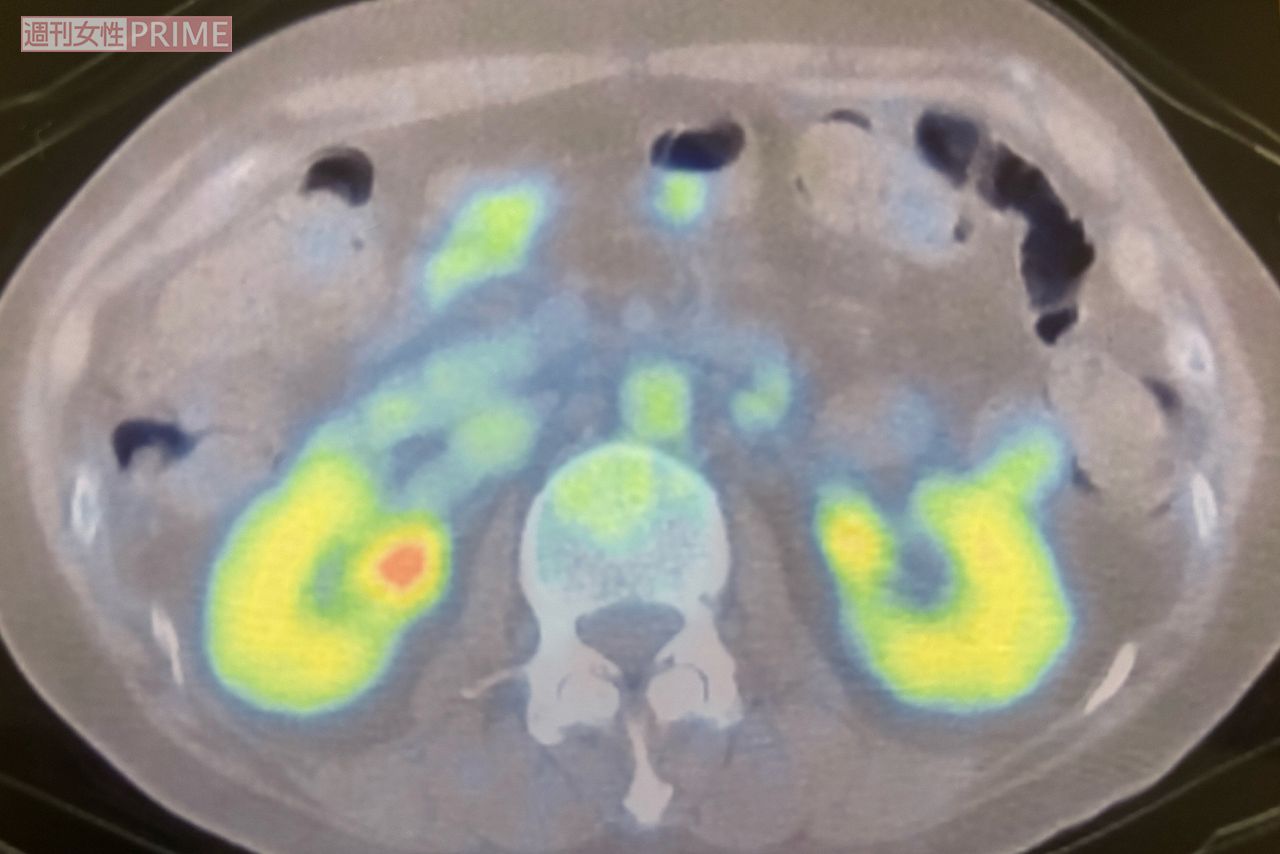

ライフ 2025/6/29 【ステージ4の子宮体がん】17歳差カップルユーチューバーのあゆみさん、余命1年宣告も「100歳まで生きる」 がん闘病離婚YouTube健康 印刷 【写真】17歳下のパートナーとあゆみさんの“仲良し”ショット 抗がん剤治療で髪が抜けることに耐えられず髪の毛を剃るも、ヨシさんは「世界一可愛い」と言葉をかけ、動画でも発信(あゆみさんのYouTubeチャンネルより) 54歳のときに、がん細胞の様子を確認するためのPET検査をした際の写真。白丸部分ががん細胞の疑いありと診断され、詳しい検査の後、抗がん剤治療をスタートすることに(本人提供) 広告を見ると、続きの写真を見ることが可能になります 続きの写真を見る ページをリロードする 記事詳細を見る facebook いいね X ポスト LINE はてなブックマークに追加 健康の記事一覧を見る タレコミを投稿する 今日の運勢を無料で見る コピーしました